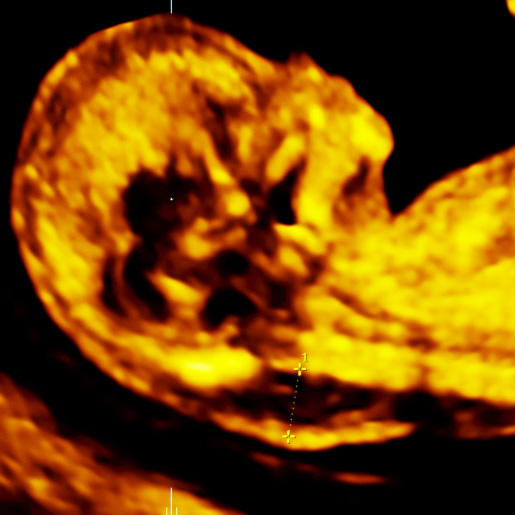

The nuchal fold is a small skin fold at the back of your baby’s neck that can sometimes look a bit thicker if certain conditions (especially trisomy 21) are present.

It is usually measured at the detailed 18–21-week scan as one of several “soft markers” that can give extra information about your baby’s health.

In most pregnancies between 15 and 20 weeks, a nuchal fold measuring less than 6.0 mm is considered normal.

If your baby’s nuchal fold is 6.0 mm or more, your report will usually describe it as “increased” or “thickened”. On its own it is a soft marker, not a diagnosis, and many babies with a thick nuchal fold are born completely healthy.

Yes. The measurement of NF is technically quite challenging and can change if the baby’s head and neck are extended or flexed, or if the baby is moving. This is why it should be done by an experienced sonographer or fetal medicine specialist, and sometimes repeated if the position is not ideal.

No. Nuchal translucency (NT) is a fluid space measured at the back of the neck in the first trimester (around 11–13 weeks).

The nuchal fold (NF) is a different measurement of the skin and underlying tissue at the back of the neck in the second trimester (around 18–21 weeks).